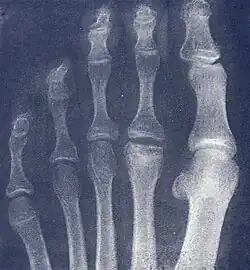

Freiberg disease as seen on plain film

2. Radiography: X-rays may reveal flattening, sclerosis, or fragmentation of the metatarsal head.

X-ray of Freiberg disease.jpg

The prognosis for Freiberg disease varies depending on the stage at diagnosis and the chosen treatment approach. Early diagnosis and appropriate management can lead to favorable outcomes, with many patients experiencing significant pain relief and improved function. However, some individuals may develop chronic pain or limitations in physical activities, particularly if the condition is left untreated or progresses to advanced stages.